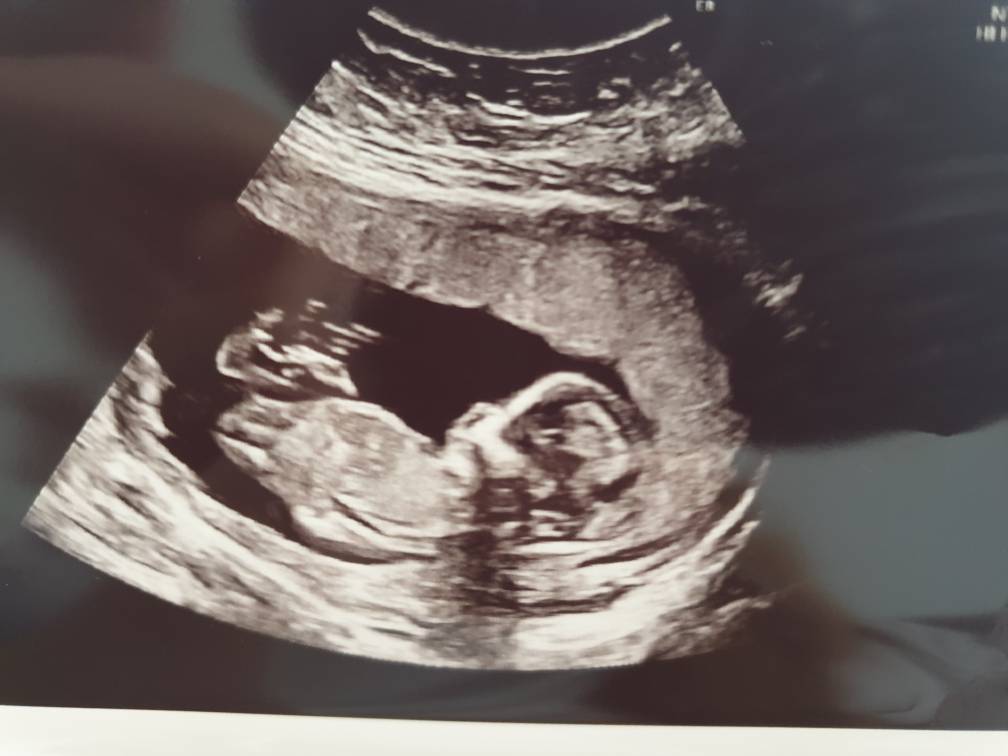

Według om 13+3 a usg 14+0 :) ginekolog mówiła, że chyba dziewczynka :) z ciekawości zdjęcie wstawiam czy wy coś widzicie bo dla mnie to czarna magia ;)Zobacz załącznik 993114

Laleczka jak sie patrzy [emoji7][emoji7][emoji7]

Dziewczynka jak się patrzy. Nie widzę żadnego stojącego nuba.

Ja tez widze dziewczynke :D